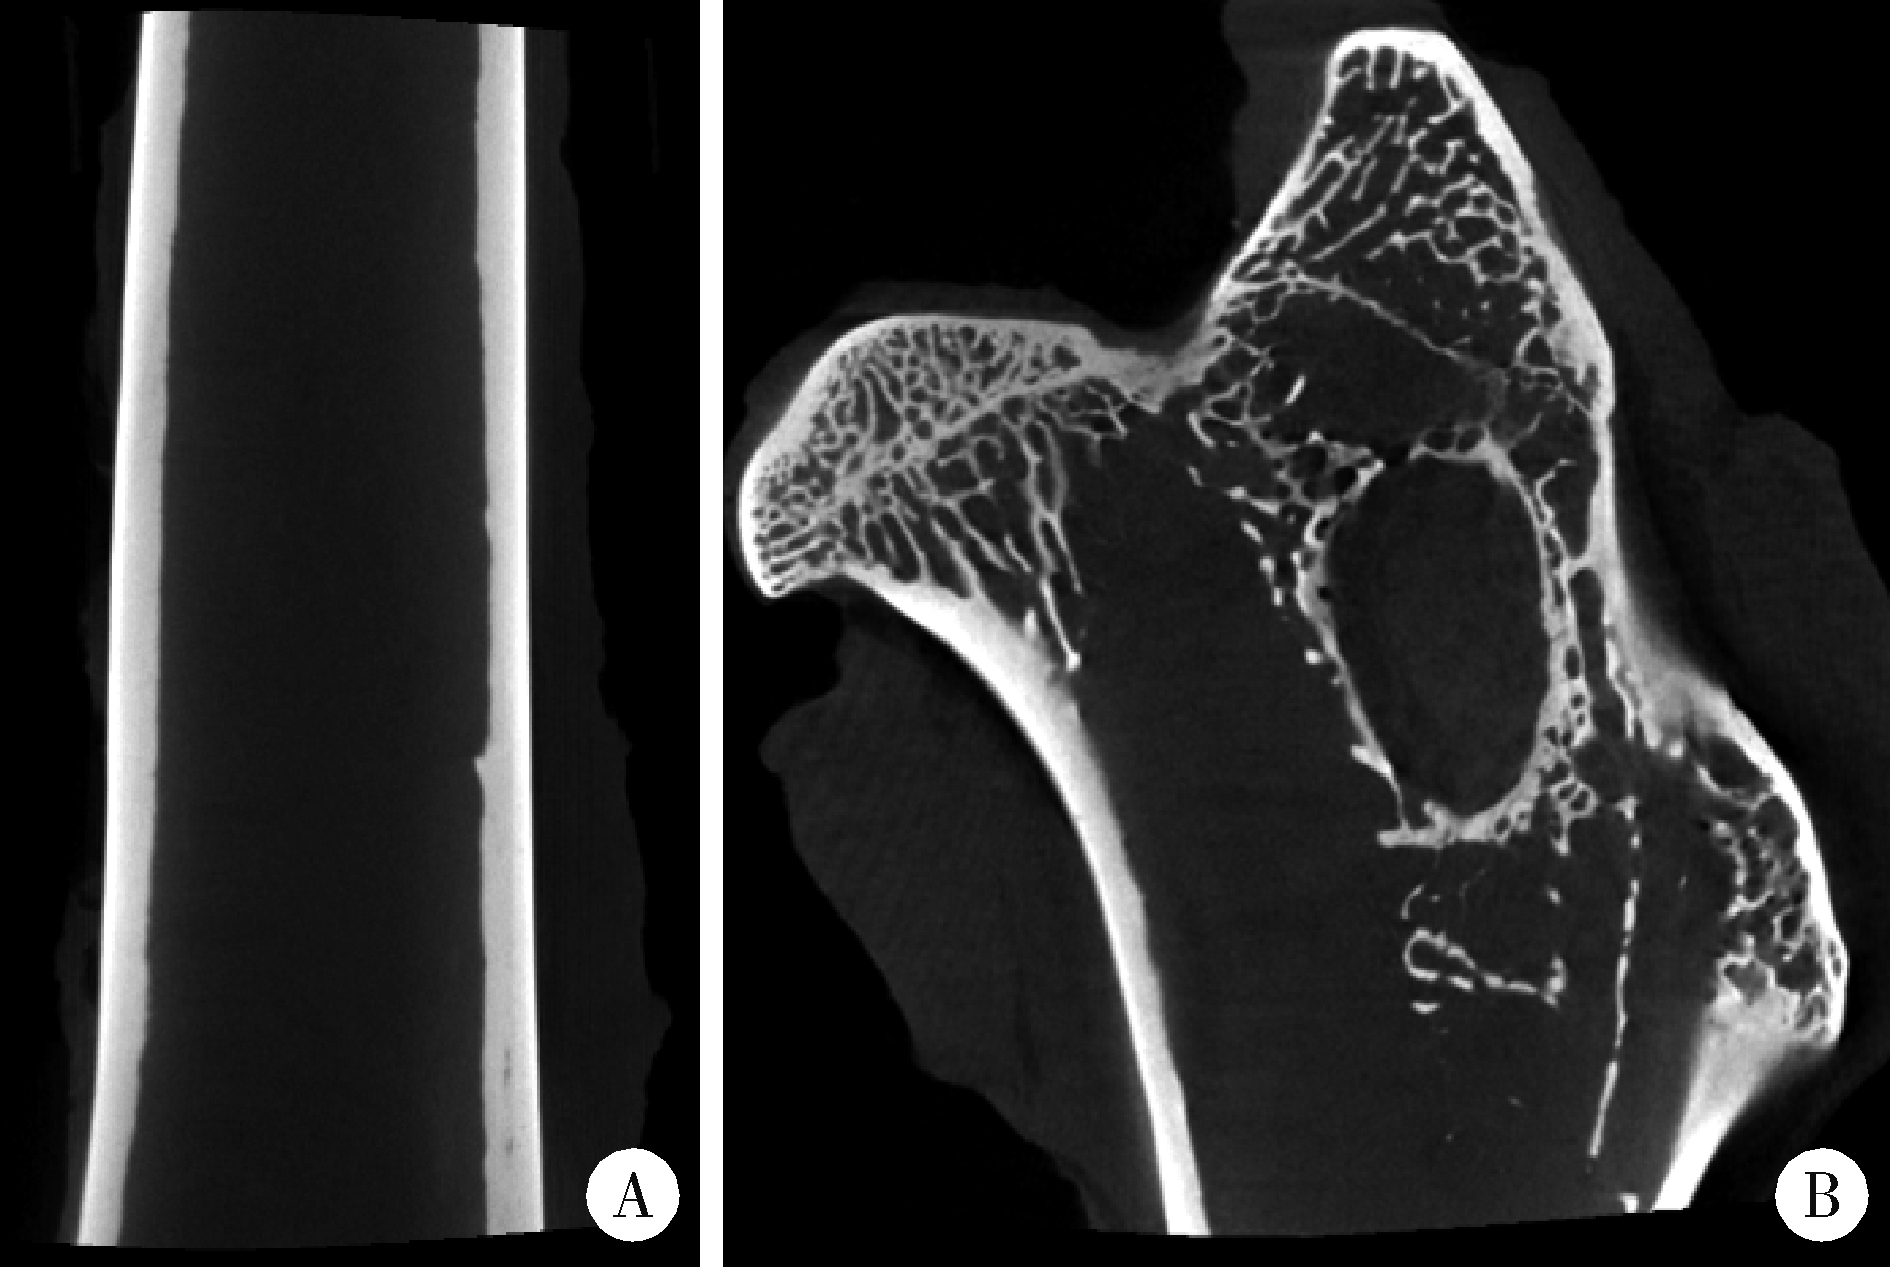

Figure 5

Radiographs of the femoral shaft and proximal femur of the experimental group at 12 weeks showed no residual gas A, femoral shaft; B, proximal femur."